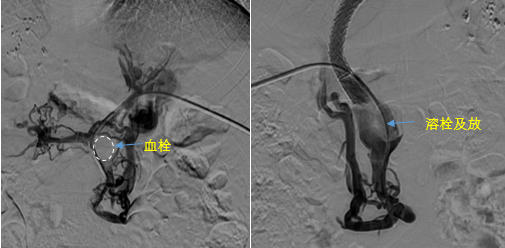

在西安國際醫(yī)學(xué)中心醫(yī)院,韓國宏教授對李女士進(jìn)行了細(xì)致的問診及檢查,在CT圖像上仔細(xì)的分析,針對患者特殊的病情制定了詳細(xì)的治療方案。第一次進(jìn)入手術(shù)室,在DSA的監(jiān)測下,造影過程中門靜脈血栓的輪廓逐漸顯現(xiàn)出來,見多識廣的醫(yī)生們也大吃一驚,發(fā)現(xiàn)遠(yuǎn)端脾靜脈及腸系膜上靜脈也存在大量血栓?;颊叩氖彻芪傅嘴o脈曲張非常嚴(yán)重,疏通堵塞的門靜脈已是刻不容緩。

見此情形,韓國宏教授憑借豐富的臨床經(jīng)驗(yàn)很快調(diào)整了策略,在超聲診療中心的協(xié)助下進(jìn)行門靜脈右支穿刺,并進(jìn)行造影,看到目標(biāo)血管后,韓國宏教授用“明修棧道,暗渡陳倉”的方法,讓來自脾臟和胃腸的血流終于暢通的回流到了肝靜脈。通過血流的沖刷以及抗凝溶栓藥物的作用,幾日后復(fù)查造影發(fā)現(xiàn)門靜脈血栓已逐漸變小,不會對回流到肝臟的血流產(chǎn)生大的阻礙作用,門靜脈的壓力顯著減小,患者再次出血的幾率也隨之降低。幾經(jīng)周折,這顆“定時炸彈”終于被拆除,李女士和她的家人多年來心里的石頭也終于落地。